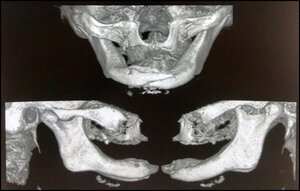

CT scans show more detailed images that may help in the differential diagnosis between jaw osteonecrosis and metastatic bone disease. There may be resorption of the trabecular bone with alteration of its structure, which will depend greatly on the size and intensity of the BAO lesion in process.28

Radiographic exam revealed an extensive osteolytic lesion in the alveolar ridge and fracture in the symphysis region with dislocation of the stumps. See Figures 5 & 6. The proposed treatment was debridement of necrotic bone plus resection of stumps with safety margin, installation of reconstructive plate previously molded in a prototyping model (Figures 7, 8 & 9), the procedure was performed in a hospital environment under general anesthesia.